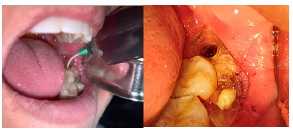

En boca del paciente se realizó PAAF (Punción por aspiración de aguja fina) obteniendo secreción hemática, de aproximadamente 1 CC, luego de descartar una lesión vascular se procedió a la toma de muestra para biopsia incisional de hueso supracortical de la lesión, en región retromolar distal a UD 37 y fragmento de membrana quística. Al momento de realizar la incisión se evidenció gasto líquido de un color blanco amarillento.

Figura 6 Manejo quirúrgico de la lesión (A) Realización del PAAF, (B) Levantamiento del colgajo. (C) Toma de muestra para biopsia incisional de hueso supracortical de la lesión en región retromolar. Fuente: Historia Clínica. Especialización Cirugía Bucal ULAC-IDOLA. 2022.